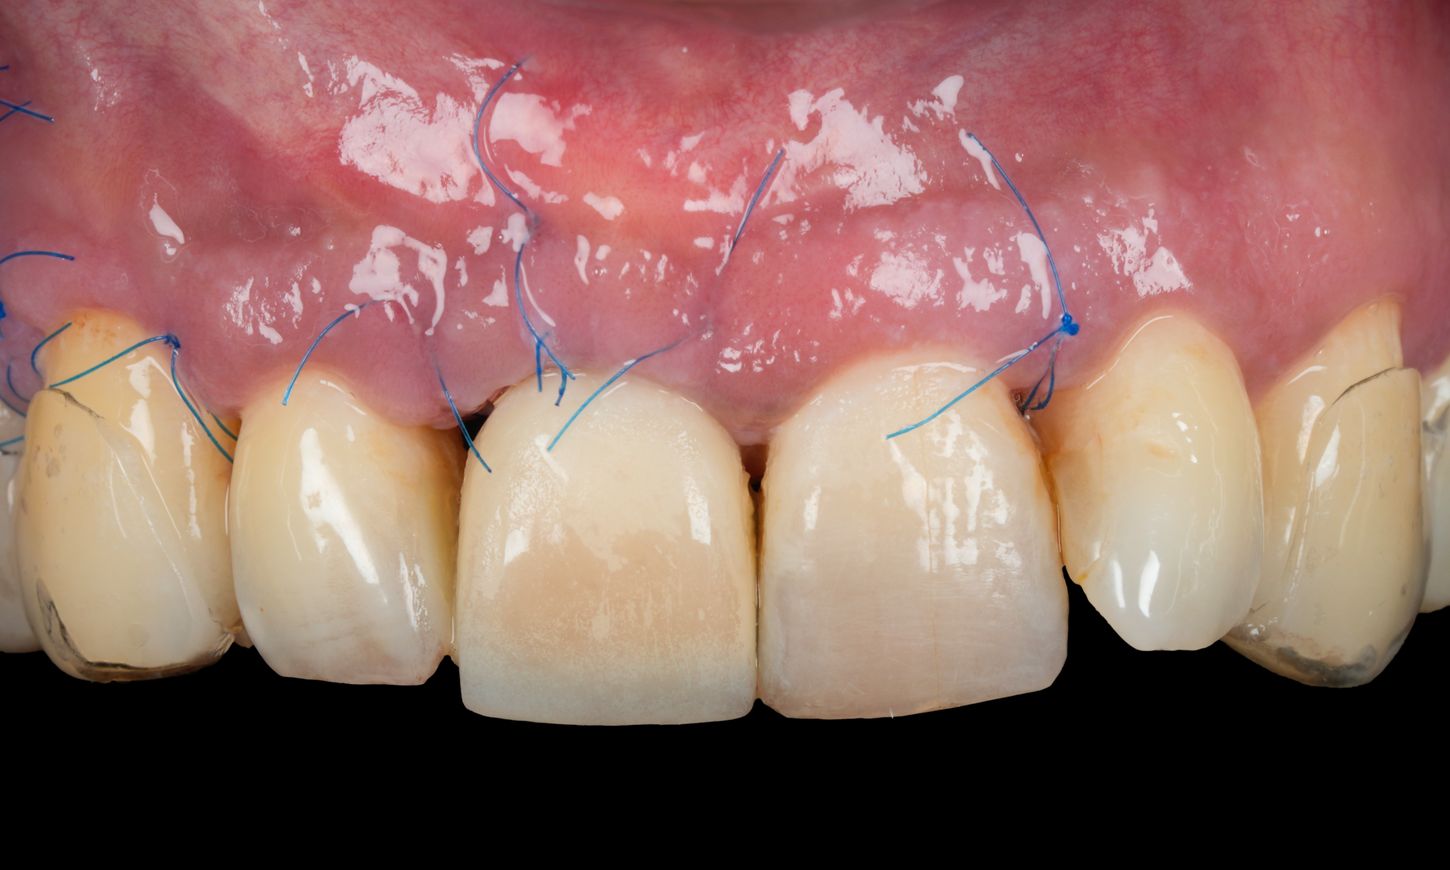

Two weeks later, the sutures were removed, and wound healing was satisfactory (Fig. 21).

Fig. 21

Three months postoperatively, the Maryland bridge was removed. The soft tissue healing was satisfactory (Figs. 22-24).